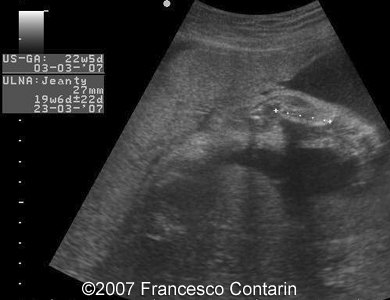

This is a 22-year-old woman (G4, P2) with unremarkable familiar history, referred to our hospital at 29 weeks of gestation due to a fetal ascites. There were no signs of maternal-fetal blood incompatibility. The ultrasound investigation revealed rhizomelia, postaxial polydactyly, small thorax, short ribs, ascites, increased abdominal biometric parameters, polyhydramnios. We supposed two diagnoses: Short rib-polydactyly syndrome versus Jeune syndrome (asphyxiating thoracic dystrophy).

Images 1, 2. 29th week of pregnancy -  shortened femur (left); and ulna (right).

1

2